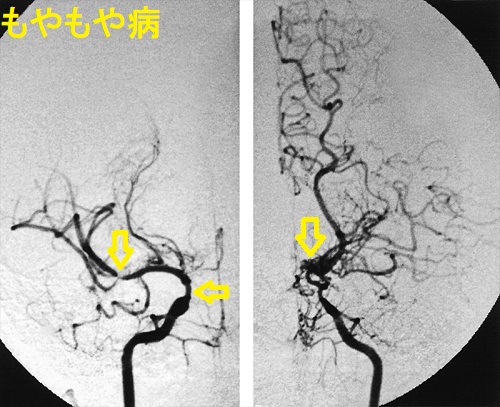

- 類もやもや病(ウィリス動脈輪閉塞症)

特に原因のはっきりしない「もやもや病(ウィリス動脈輪閉塞症)」は、内頸動脈末端と前中大脳動脈部が狭窄・ 閉塞し、基底角部の異常血管網(もやもや血管)が発達する謎の病気です。

甲状腺機能亢進症/バセドウ病など基礎疾患がある場合、「類もやもや病」と言われ、甲状腺治療開始後に脳虚血症状も改善する報告が多くあります。状況によっては(改善が見込めない場合)、甲状腺機能改善後に脳神経外科で脳血行再建術を行う事になります。

甲状腺機能亢進症/バセドウ病に合併する類もやもや病の原因は不明です。可能性として、

- 甲状腺ホルモンによる交感神経亢進状態で血管収縮(Gen Pharmacol. 2000 Jun;34(6):429-34.)

- 循環血液量増大・心拍出量増大・頻脈による血管内皮障害(Biomed Pharmacother. 2002 Jul;56(5):241-6.)(Sci Rep. 2020 Apr 24;10(1):6992.)

- 共通の自己免疫 (Stroke. 2011 Apr;42(4):1138-9.)(Stroke. 2010 Jan;41(1):173-6.)

もやもや病(ウィリス動脈輪閉塞症)では甲状腺自己免疫抗体の陽性率が高いとされ、共通の自己免疫が考えられます。

もやもや病(ウィリス動脈輪閉塞症)の約50%で甲状腺自己抗体[抗甲状腺ペルオキシダーゼ抗体(TPO抗体)、抗サイログロブリン抗体(Tg抗体)、TBII(第一世代のバセドウ病抗体)]が認められる(対照群20.0%)(Stroke. 2010 Jan;41(1):173-6.)

もやもや病(ウィリス動脈輪閉塞症)の甲状腺機能亢進症、潜在性甲状腺機能亢進症、潜在性甲状腺機能低下症患者の比率、および抗甲状腺ペルオキシダーゼ抗体(TPO抗体)・抗サイログロブリン抗体(Tg抗体)の陽性率は、健常対照群より有意に高い(Stroke. 2011 Apr;42(4):1138-9.)。